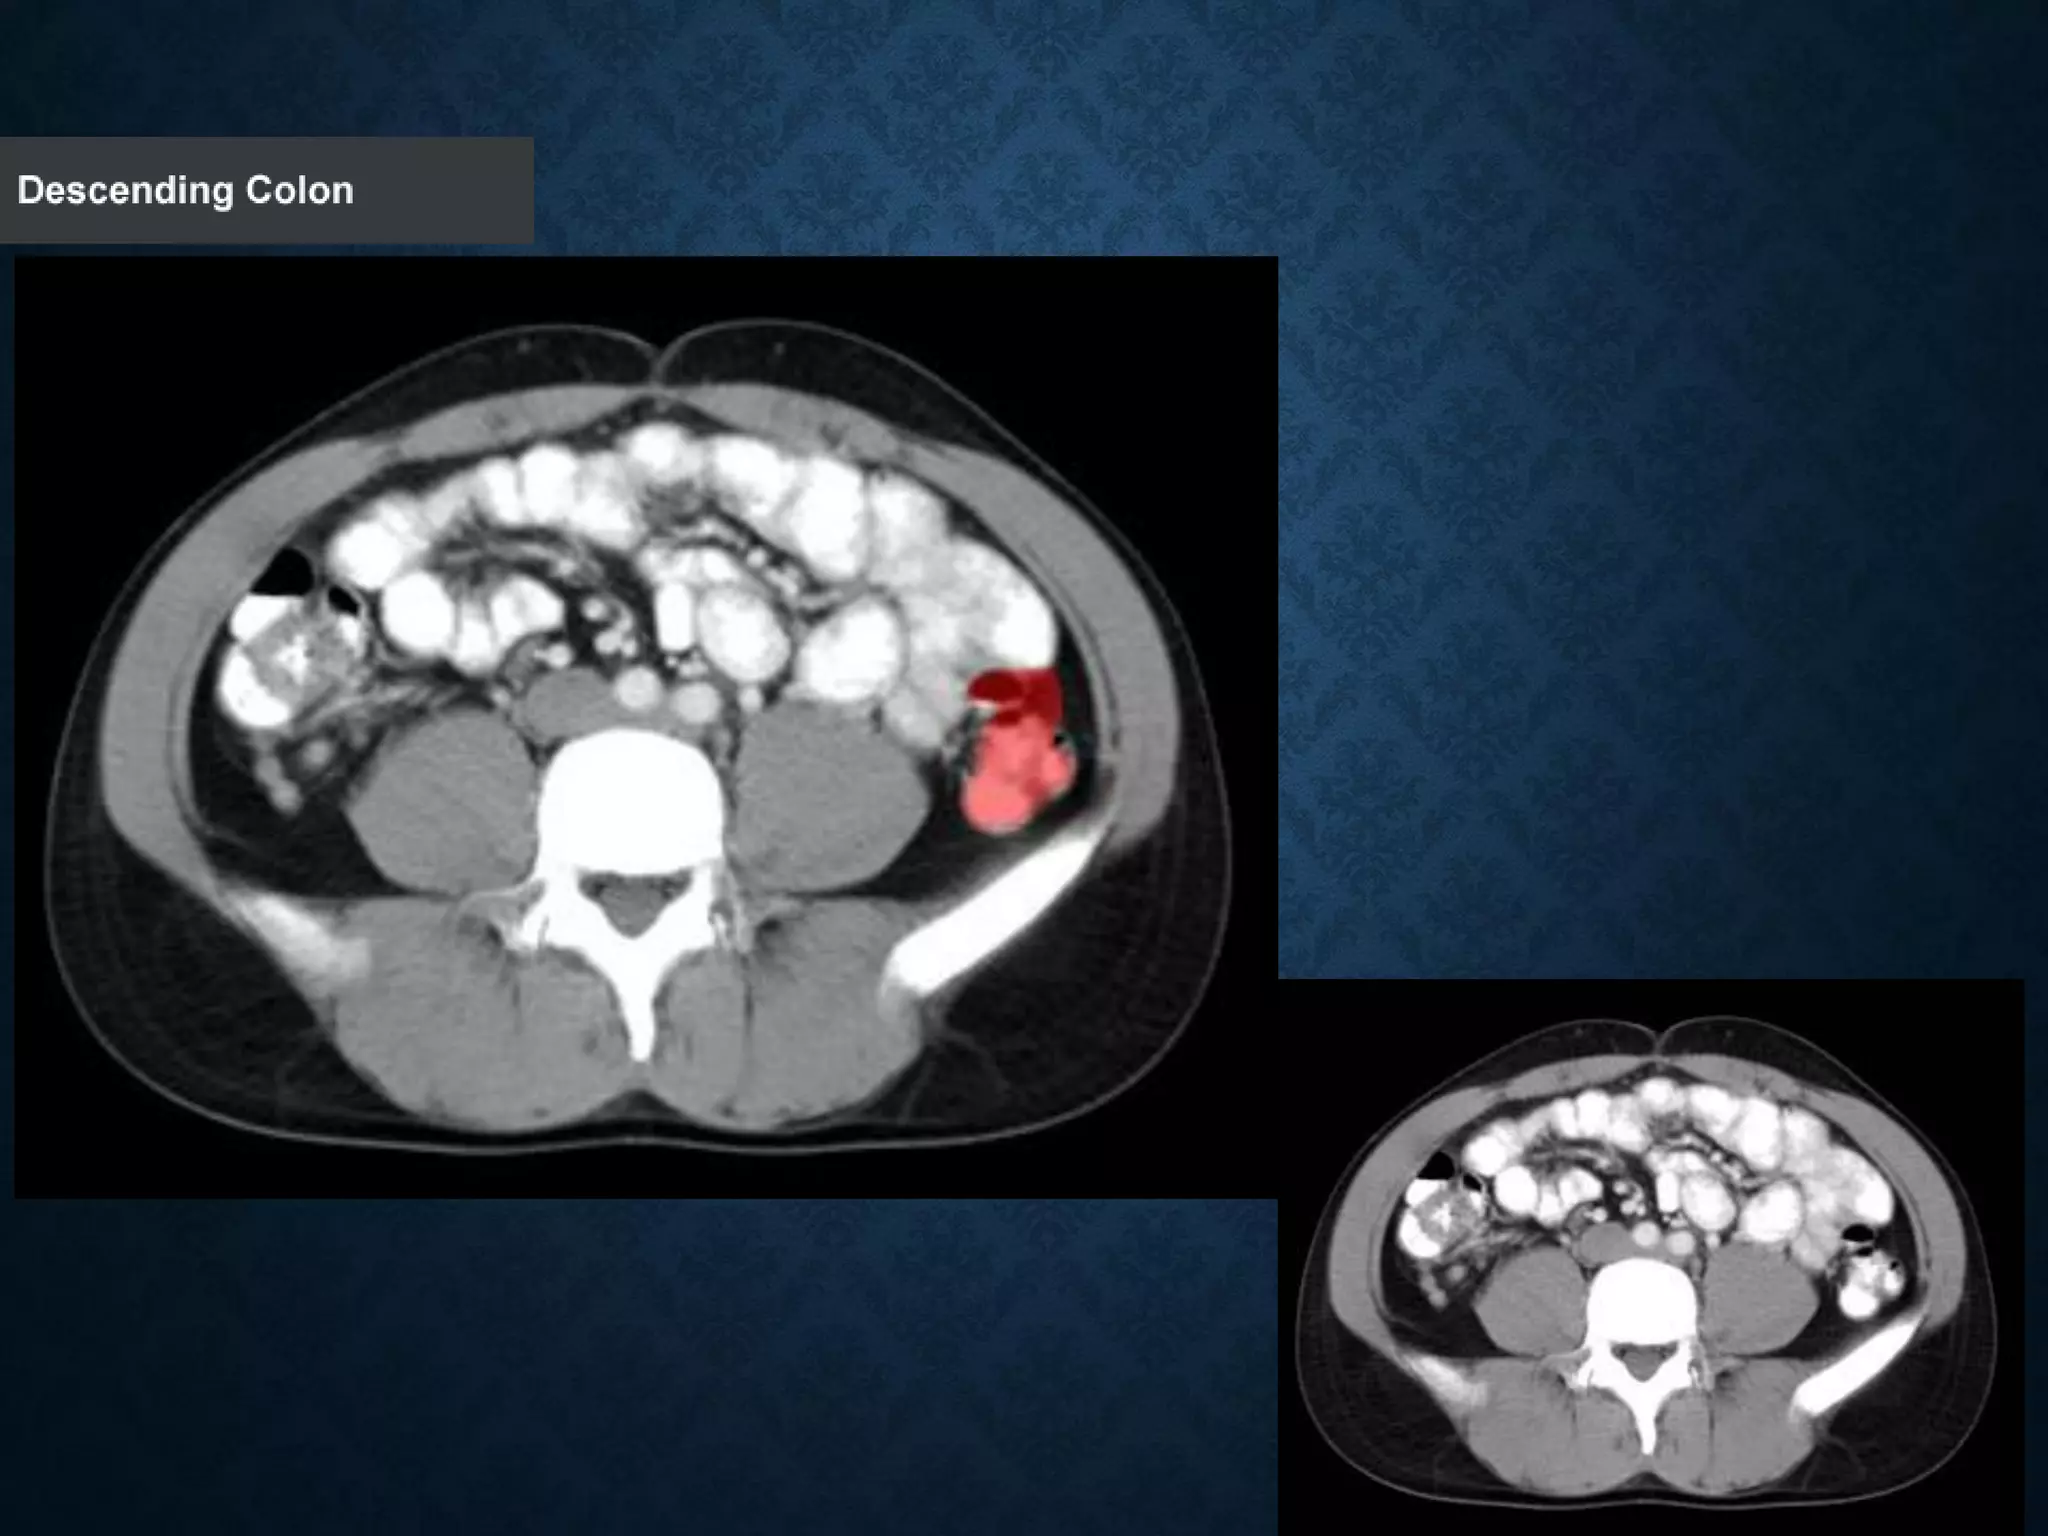

Identify the following structures in the body CT to the right. To view the location of the structure in the image click on

the label at the left and the structure will be indicated in the image. Abdominal CT scans typically begin just above

the diaphragm, so the first slice you see is of the lower chest.